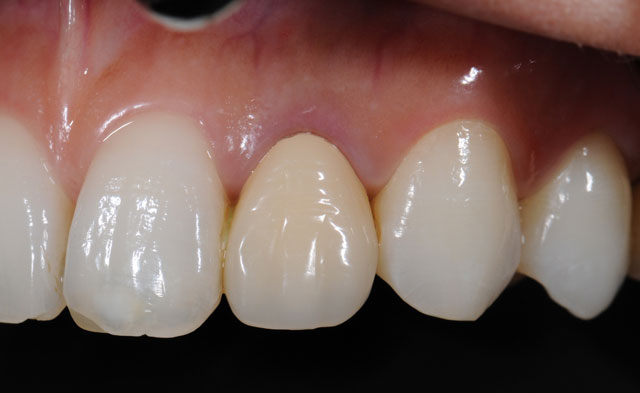

5.かぶせ物を装着します

• 型取りをして作るので、原則2回かかります。

• 通常、歯の全周を覆う形になります。

もとの虫歯の範囲が狭い場合は、部分的な詰め物ですむ場合もあります。

• 保険内のものと保険適応外のもので材質や作り方が異なります。

保険適用のかぶせ物

保険適用外のかぶせ物

これらのかぶせ物の特徴や性質については「審美治療」をご覧ください。